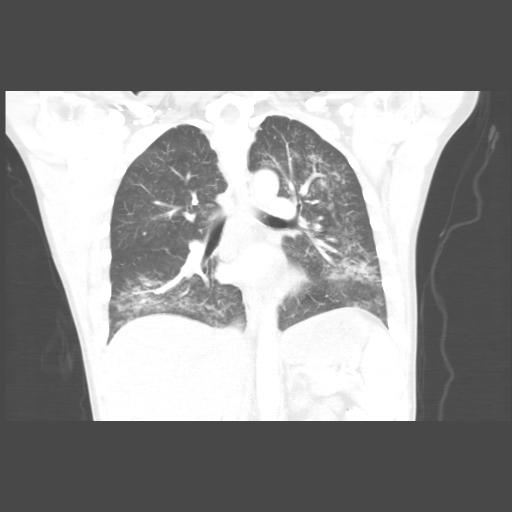

As lung injuries from vaping continue to rise across the United States, Rochester physicians and New York health leaders developed a new tool to assist in the diagnosis and treatment of e-cigarette, or vaping, product use associated lung injury (EVALI).

The nationwide epidemic began in the spring and to date, the CDC has charted more than 2,000 cases, including 40 deaths. The cause of the illness remains a mystery, though many patients used products containing THC, the psychoactive component in marijuana. Patients experience devastating lung injury, some requiring long hospitalizations and treatment in the intensive care unit, followed by a slow recovery.